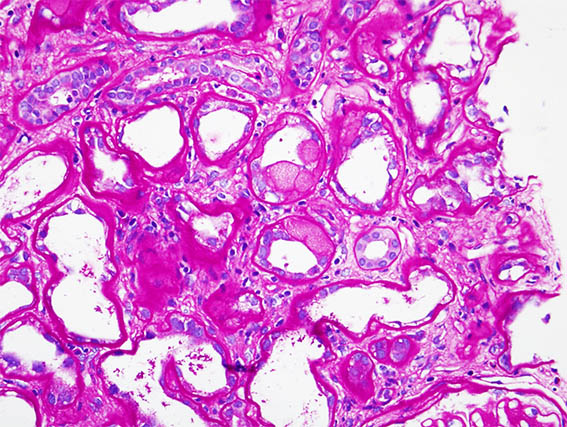

The patient is a 41-year-old woman with diabetes, who developed abrupt nephrotic syndrome, for which a kidney biopsy was performed. The biopsy shows advanced diabetic nephropathy without superimposed GN.

There is an area of tubular lesions as in the images:

Figure 3. PAS, X400.